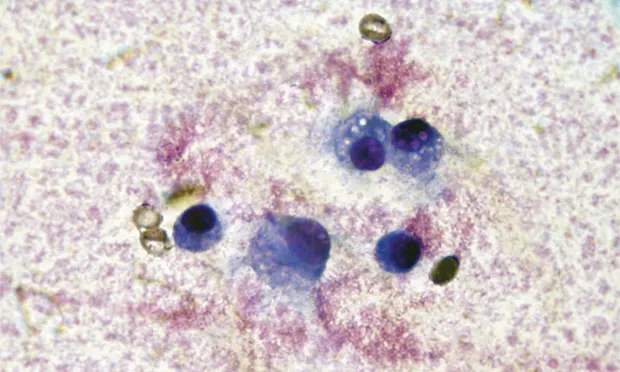

Two major groups of arthropathy are nonsuppurative inflammatory and suppurative inflammatory. Nonsuppurative inflammatory conditions, such as degenerative joint disease (DJD; eg, cruciate ligament rupture, elbow dysplasia, hip dysplasia, chronic joint trauma), trauma, and hemarthrosis typically have a total WBC count less than 5000 cells/µL with mononuclear cells predominating (Table). Macrophages may have phagocytic vacuoles and phagocytized cartilage fragments in cases of DJD (Figures 1 & 2).

FIGURE 1 Cytology of joint fluid showing predominance of mononuclear cells with vacuolar inclusions, commonly seen in patients with DJD.